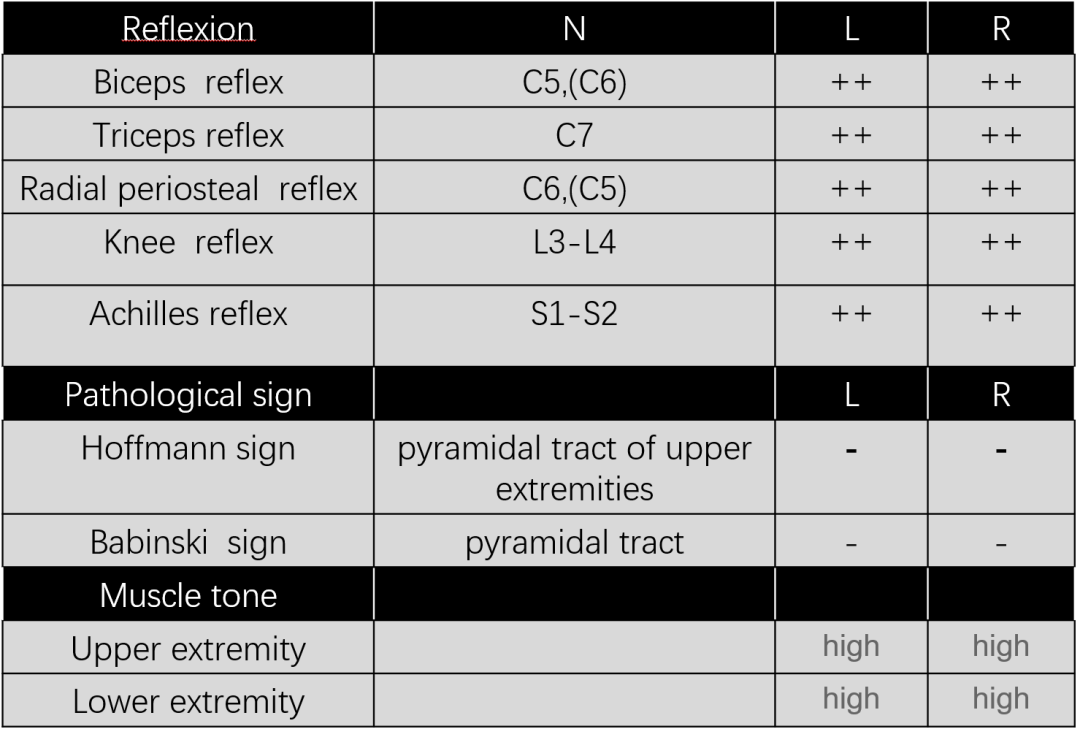

Diagnosis:

腰椎侧后凸畸形

腰椎陈旧性压缩性骨折(L4)